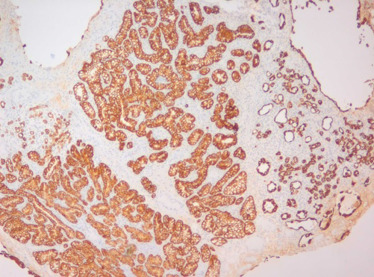

O estudo anatomopatológico revelou tratar‐se de uma lesão epitelial constituída por estruturas tubuloglandulares revestidas por células cuboides de citoplasma claro, com infiltrado inflamatório linfoplasmocitário e edema do estroma associados (fig. 1 ). Não se identificaram nucléolos, mitoses, necrose nem desmoplasia. Algumas estruturas continham mucinas neutras (PAS  +) e mucinas ácidas (Alcian Blue +) intraluminais (fig. 2 ). O estudo imunohistoquímico mostrou expressão de citoqueratina 7 (fig. 3 ), P504s (alfa‐methylacyl coenzime A racemase [AMARC]) (fig. 4 ) e índice proliferativo (Ki67/mib1) baixo, inferior a 2%. Para o diagnóstico diferencial foram também estudados outros anticorpos: citoqueratina 20, p53, p63, CA125 e CEA, que foram negativos. Pelas características morfológicas e imunohistoquímicas, foi realizado o diagnóstico de adenoma nefrogénico da bexiga.

Estruturas tubuloglandulares revestidas por células cuboides de citoplasma claro ...

Figura 1.

Estruturas tubuloglandulares revestidas por células cuboides de citoplasma claro (setas), com infiltrado inflamatório linfoplasmocitário e edema do estroma associados (Hematoxina/Eosina; 200 x).

Estudo imunohistoquímico – expressão de citoqueratina 7; (100 x).